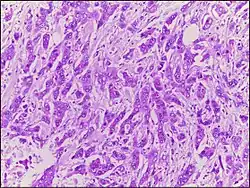

Micrograph of breast tissue with ductal carcinoma. H&E stain.

Ductal carcinoma is a type of tumor that primarily presents in the ducts of a gland.[1]